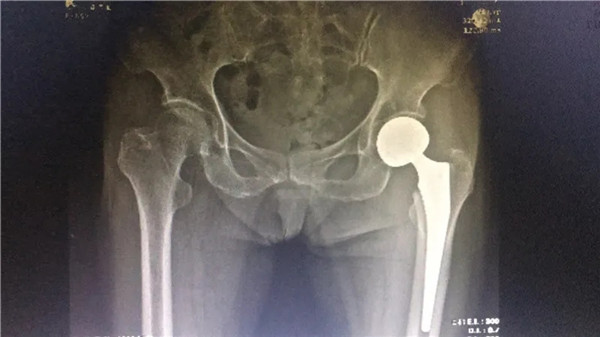

術(shù)后

6月4日,在完善各項(xiàng)術(shù)前檢查,身體狀況符合手術(shù)指征后,陳阿婆接受了左髖關(guān)節(jié)置換術(shù)。手術(shù)由危立軍副院長(zhǎng)主刀,一個(gè)半小時(shí)后,手術(shù)圓滿成功。術(shù)后,陳阿婆恢復(fù)良好,一周后,便可以下地行走。術(shù)后半個(gè)月,陳阿婆出院回家休養(yǎng)。